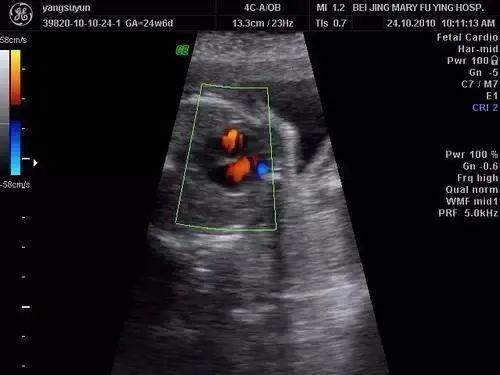

如果胎儿脑室内有多个亮点,且亮点大于5毫米,或同时有其他超声软指标异常,也可能是病理性的,可能与胎儿染色体畸形有关,其中以唐氏综合征最为常见。应进一步做无创DNA或羊穿检查,以消除婴儿染色体异常。如果检查完全正常,不用担心,强回声点会逐渐被吸收。